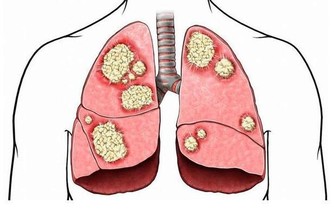

▴海藻又名海帶花、落首、烏菜、海蘿等。現代藥理研究稱,海藻的粗提物對子宮癌-14、肉瘤-180、淋巴1號腹水型的動物移植腫瘤有一定的抑制作用;同屬植物褐藻熱水提取物的非透析部分,對小鼠皮下移植的肉瘤-180抑制率高達93.7%(腹腔給藥連續10天)。實驗小鼠口服含海藻的復方煎劑,對艾氏腹水癌有抑制作用。